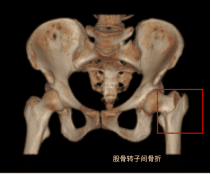

一、什么是股骨转子间骨折?

指股骨颈基底至小粗隆下平面区域内的骨折,好发于中老年骨质疏松患者。患者多数会有明确外伤史,最常见的原因是跌倒,髋部直接着地,大部分老年人比较瘦弱,髋部骨头紧邻皮下,无缓冲作用,加上老年人合并骨质疏松,当下肢突然扭转、跌倒、轻微的外力即可以引起该处骨折。

三、需要进行哪些辅助检查?

X片: CT: